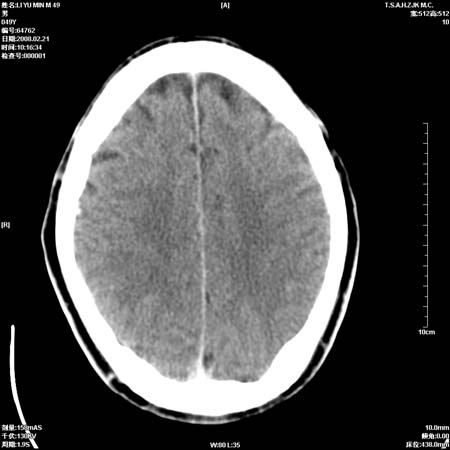

一周后复查ct:

可能为正常。间隔一周蛛血应基本吸收;再过一周复还是这样应该可以肯定了。

一周时间密度未见改变,考虑为正常图像(脑动脉硬化?)。